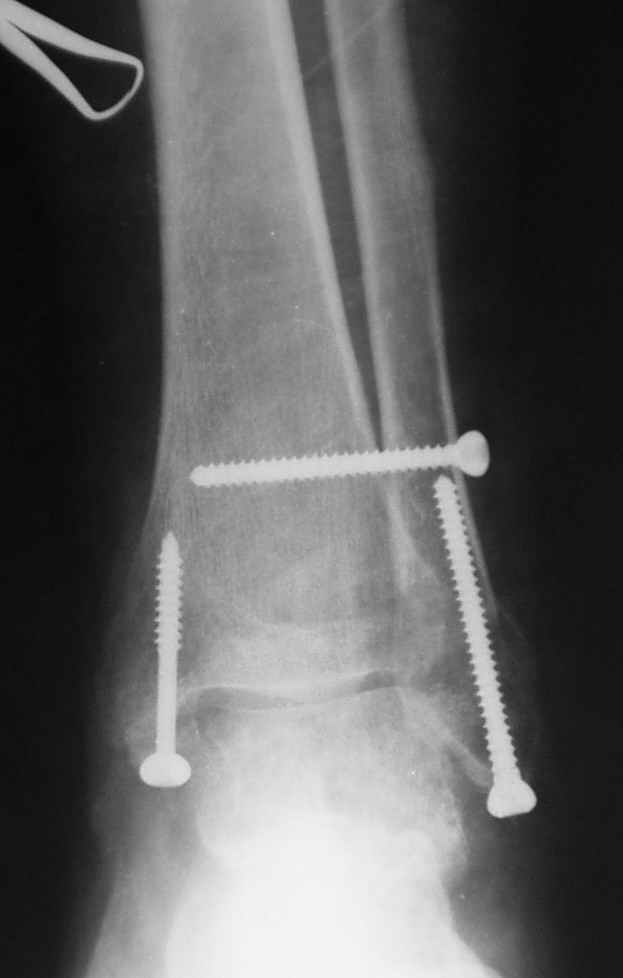

Ниже рентгенограммы

До операции 28 июля

Операция 29 июля

Через месяц

Риторический вопрос - в каком руководстве рекомендован такой способ остеосинтеза наружной лодыжки?

Очевидно, такой результат операции был запрограммирован. При невосстановленной длине и практически нефиксированной малоберцовой кости (этот кортикальный винт - как карандаш в стакане), при неустраненном подвывихе, невправленной и тоже нефиксированной внутренней лодыжке нет стабильной вилки сустава. Если такую операцию сделать даже сразу, а не через 4 месяца, то результат ожидаем

тот же.

Вообще говоря, такое повреждение вполне успешно можно лечить без операции - если 6 недель подержать в гипсовом "сапожке" с хорошо устраненным подвывихом. Вероятное несращение внутренней лодыжки не обязательно компрометирует результат.

Ну а уж если выбран остеосинтез - нначать надо было с репозиции малоберцовой кости с точным восстановлением длины, с фиксацией треть-трубчатой пластиной по задней поверхности. Позиционный винт

избыточен - повреждение практически подсиндесмозное. А если бы

действительно было повреждение синдесмоза - в 4 месяца позиционный винт - не решение. Внутренню лодыжку такую - надо было бы спицами и проволочной петлей. Извините за эти банальности.